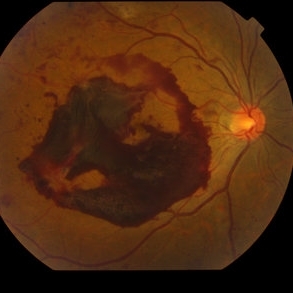

Proliferative Diabetic Retinopathy with Subhyaloid hemorrhage

Oct 18 2012 by Suber S. Huang, MD, MBA, FASRS

43 year old diabetic man with proliferative diabetic retinopahty, subhyaloid hemorrhage, ischemia, neovascuarization.

Photographer: Stacie Hrvatin

Condition/keywords: ischemia, retinal neovascularization, subhyaloid hemorrhage